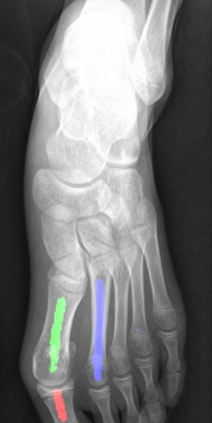

Angular measurements is essential to make a resonable treatment for Hallux valgus (HV), a common forefoot deformity. However, it still depends on manual labeling and measurement, which is time-consuming and sometimes unreliable. Automating this process is a thing of concern. However, it lack of dataset and the keypoints based method which made a great success in pose estimation is not suitable for this field.To solve the problems, we made a dataset and developed an algorithm based on deep learning and linear regression. It shows great fitting ability to the ground truth.